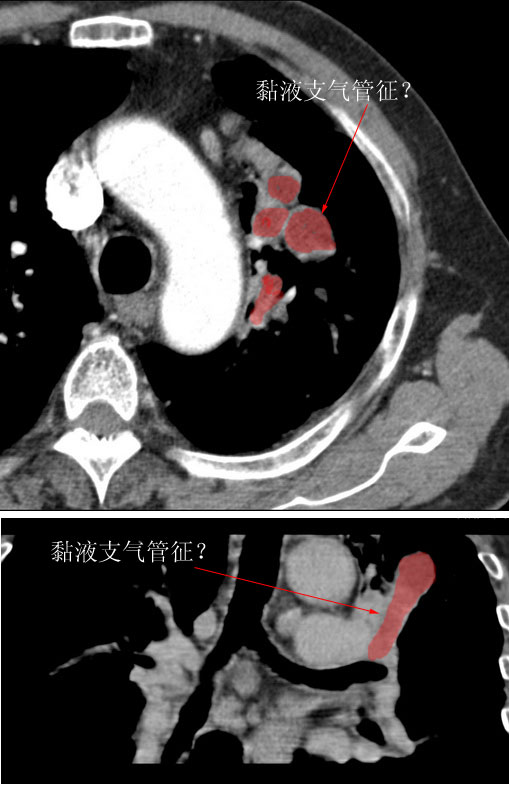

肿块贴近左肺门,包绕左上肺动脉,形态不规则。肿块增强扫描中度强化。纵膈内主动脉弓左旁间隙、气管隆突前、下间隙见多枚淋巴结影。综上考虑左侧中央型肺癌可能性大。图片没有完整上传,尤其是左肺上叶支气管分支层面没有上传,因此不好判断是叶支气管中断还是段支气管中断。另外,下图红色部分所示是“黏液支气管征”吗?